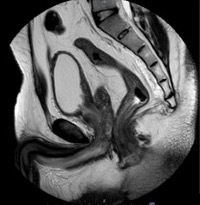

Cystitis cystica et glandularis (CCEG) is a rare hyperproliferative lesion of the bladder mucosa resulting from chronic inflammation or obstruction. It is marked by glandular metaplasia of transitional cells, leading to a cystic appearance due to the proliferation of Von Brunn islets, which cause invagination of the transitional epithelium into the lamina propria. Imaging characteristics are nonspecific and resemble those of a bladder mass. Cystoscopic findings typically show bullous edematous lesions or papillary lesions with gelatinous surfaces, often affecting the trigone area. The involvement of the trigonal region can complicate the identification of ureteric orifices, posing a risk of resection-related injury. Our goal is to highlight the clinical behavior, radiological and cystoscopic features, and propose a management algorithm to minimize deterioration of renal function.

45 patients were included, 95% were men, with mean age of 35 years. Most common presenting feature was lower urinary tract symptoms (90%), with hematuria (30%), flank pain in 10%. Seventy percent patients had uppertract changes. Imaging findings are consistent with bladder mass and cannot distinguish cystitis cystica from carcinoma of bladder. Thirty percent of patients had recurrence of lesions with average time to recurrence being 13 months. Ten percent of patients underwent ureteric reimplant.